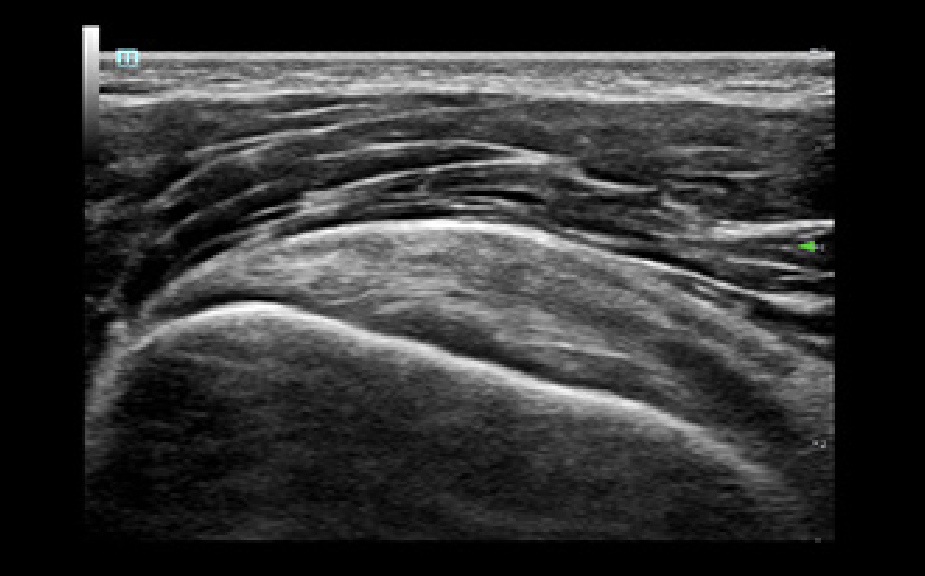

El sistema de ultrasonido TE9 estĂĄ dise?ado para ayudar a facilitar una mejor atenciĂłn al paciente y ampliar las capacidades de imagen para aplicaciones de anestesia, emergencias y cuidados crĂticos. Con funciones avanzadas, una gran pantalla tĂĄctil y una tecnologĂa de imagen superior, el TE9 es ideal para ayudar a mejorar la eficiencia clĂnica y la confianza en el diagnĂłstico. Las herramientas de automatizaciĂłn inteligentes brindan mediciones rĂĄpidas y reproducibles para exĂĄmenes y procedimientos fiables, incluso en entornos de gran presiĂłn.

SoluciĂłn de punciĂłn para un solo operador